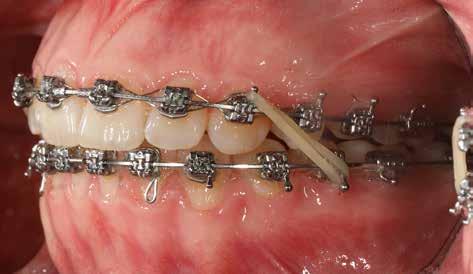

A Pitts21-es fix készülékes kezelés során a harapásemelőket a felső nagyőrlő fogakra ragasztottuk, hogy a felső molárisok intrúziójával segítsék a harapás zárását (8. kép) Ún. keresztharapásos, majd később normál class 2-es gumihúzással (9–10. képek), továbbá az elülső fogakon alkalmazott ún. Rainbow harapás-záró gumihúzással (11. kép) korrigáltuk a jobb oldali teljes premolárisnyi distal-harapást, valamint az elülső nyitott harapást.

6 hónap után a nyitott harapás már nagyjából összezárásra került (12. kép)! A gumihordás a kezelés teljes hosszában folyamatos, éjjel-nappal, 22-24 órában az étkezések és az utánuk történő fogmosás kivételével.